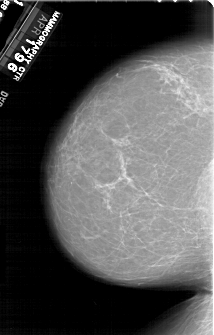

A_1923_1.RIGHT_MLO

RIGHT_MLO LINES 6526 PIXELS_PER_LINE 3976 BITS_PER_PIXEL 12 RESOLUTION 43.5 OVERLAY

FILE: A_1923_1.RIGHT_MLO.OVERLAY

TOTAL_ABNORMALITIES 1

ABNORMALITY 1

LESION_TYPE CALCIFICATION TYPE PLEOMORPHIC DISTRIBUTION CLUSTERED

ASSESSMENT 4

SUBTLETY 2

PATHOLOGY BENIGN